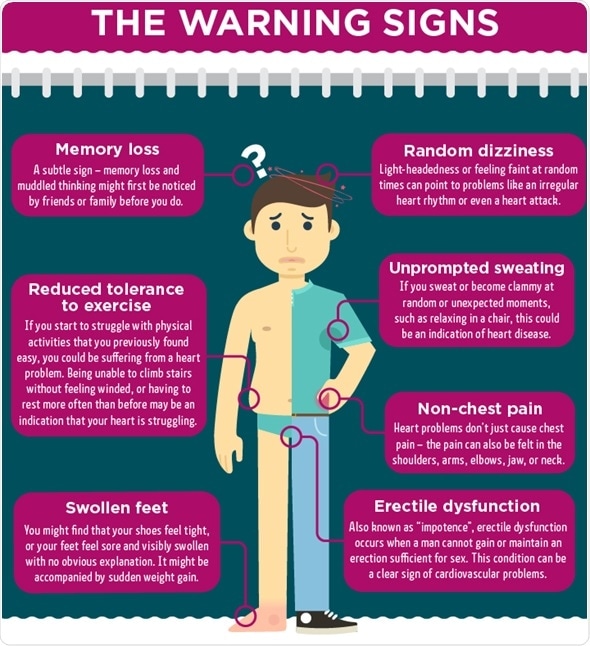

Swollen feet

A tightness in your shoes or visible swelling of your feet can indicate a heart problem. This can occur as a result of slowed circulation – as blood flows out of the heart at a slower rate, blood returning to the heart gets backed up. You may then witness a build-up in the tissues surrounding the feet, legs and ankles.

Erectile dysfunction

In men, erectile dysfunction (ED) can be a strong indicator of issues with your heart and circulatory system. It occurs when the tiny blood vessels feeding the penis don’t receive enough blood to maintain an erection sufficient for sex. ED can present itself far in advance of other symptoms, so it’s a good idea to watch out for it and act early.

Referred pain

Pain related to heart problems can occur in places other than the chest. You can experience ‘referred pain’, which occurs when pain messages running down nerves overwhelm nearby nerves. Referred pain linked to heart problems usually occurs in the shoulders, arms, jaw and neck.

Difficulty doing physical tasks

Struggling to execute simple physical tasks is a clear sign of a struggling circulatory system. You may find yourself short of breath when climbing the stairs, or feel a need to rest more often than in the past when exercising. This can indicate a reduction in your heart’s ability to supply your muscles with an oxygen-rich flow of blood.

Memory loss

Confusion and muddled thinking may indicate that your brain is not receiving a sufficient amount of blood. If left unaddressed, this can seriously damage your brain cells and lead to memory loss.